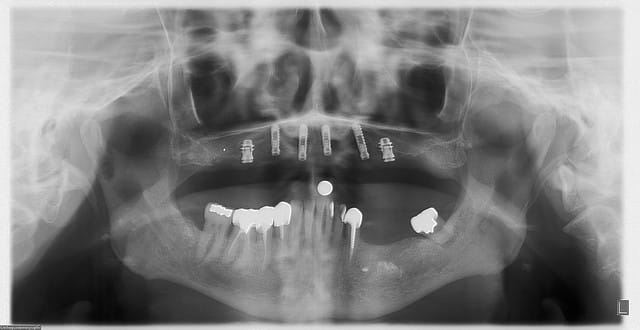

allez, dans ma série, "je remets des sujets" je vous donne quelques nouvelles de ce cas

la raison et vos conseils me sont revenus, j'ai posé hier 2 implants supplémentaires en 17 et 27 (sans les facturer à mon patient)

ce qui me frappe, tout de même, avec les quelques radios prises, c'est la cicatrisation osseuse au niveau de ceux en 15 et 25 (cf panos jour de la pose/3mois/4mois et les "zooms" pose/4mois)